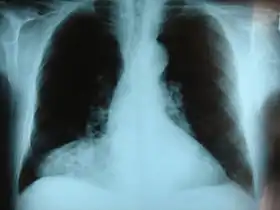

وفى أعلى البطن، يحدث"الفتق الحجابي" عندما يبرز جزء من المعدة أو الأمعاء في جوف الصدر من خلال خلل في الحجاب الحاجز.

والفتق الفجوي نوع خاص ومختلف فمن خلال فتحة حجابية طبيعية وخاصة بالمريء عندما يلتقي بالمعدة تبرز المعدة من خلال هذه الفجوة. وهذا الفتق نوعان: النوع الأول انزلاقي وهنا تبرز الوصلة التي بين المريء والمعدة إلى التجويف الصدري والنوع الآخر غير انزلاقي (بجانب المريء) حيث يبرز جزء آخر من المعدة غير الجزء الخاص بالفتق الانزلاقي وتكون الوصلة ثابتة. والفتق غير الانزلاقي (بجانب المريء) من الممكن أن يكون خطيراً حيث يمكن للمعدة أن تلتف حول نفسها وتنسد. وينصح عادة بإصلاحه.

الفتق الحجابي أو فتق الحجاب الحاجز

يحدث على مستوى أعلى في البطن، عندما يبرز جزء من المعدة أو الأمعاء إلى تجويف الصدر من خلال ضعف أو ثقب في الحجاب الحاجز. في حالات معينة من هذا النوع، يعمل الممر الطبيعي الذي يلتقي المريء من خلاله بالمعدة بمثابة "عيب أو ثقب" وظيفي، مما يتيح لجزء من المعدة أن "ينفتق" بشكل دوري إلى الصدر.

قد يكون الفتق الحجابي إمّا "انزلاقي"، عندما تدخل منطقة الالتقاء المريئي المعدي نفسها من خلال الثقب إلى الصدر، أو "غير انزلاقي" (المعروف أيضا باسم جانب المريئي)، وفي هذه الحالة تبقى منطقة الالتقاء المريئي المعدي نفسها ثابتة بينما جزء آخر من المعدة يتحرك نحو الأعلى من خلال هذا الثقب. والنوع الأخير هذا يمكن أن يكون خطيراً لأنه قد يتيح للمعدة الالتفاف والانسداد. وعادةً يُنصح بإجراء إصلاح لهذا النوع من الفتق.

الفتق الحجابي الخلقي مشكلة معروفة، وتحدث في ما يصل إلى 1 من كل 2000 ولادة، والتي تتطلب جراحة الأطفال. الأجهزة المعوية تنفتق من خلال عدة أجزاء من الحجاب الحاجز، من الجهة الخلفية الوحشية (في مثلث بوكدالك، مما أدى إلى فتق بوكدالك)، أو الجهة الأمامية الإنسية - خلف عظمة القصّ (في شق لاري/ ثقب مورغانيي، مما أدى إلى فتق مورغانيي- لاري، أو فتق مورغانيي).[10]